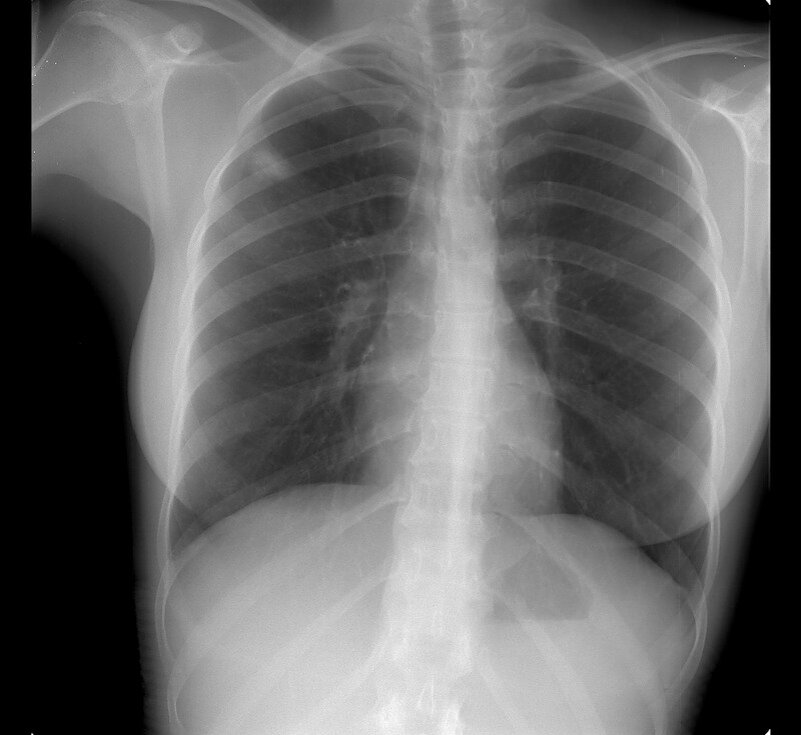

Доктор смотрит на снимки грудной клетки пациентки. Видит, около лёгочных полей тени. Неужели туберкулёз у такой молодой красивой девушки? Странно как-то.

И тут доктор наблюдает такую странность. Если снимок отвести подальше от глаз, то тени начинают превращаться в подозрительные буквы. Ну мистика какая, ей Богу. И тут он понимает, что буквы превращаются в единое слово. GUCCI.

Выяснилось, что пациентка постеснялась снять майку на бретелях перед лаборанткой. А на бретелях как раз и была та сама надпись GUCCI. Получился очень "модный" снимок!